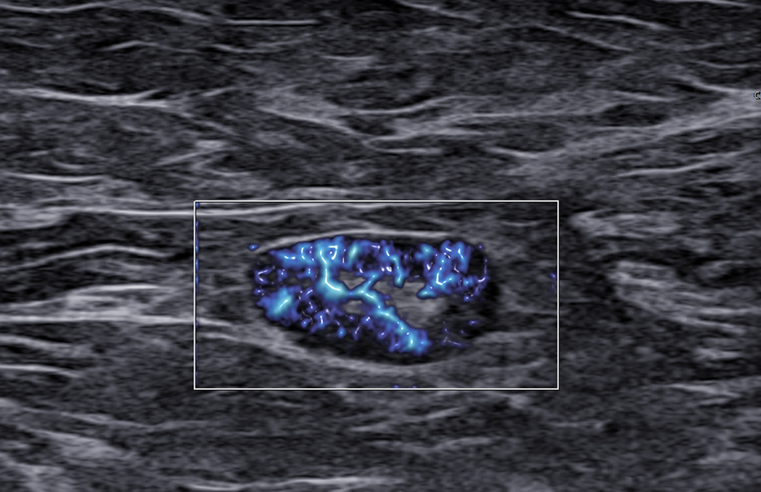

Rak piersi a obraz węzłów chłonnych. LN-RADS